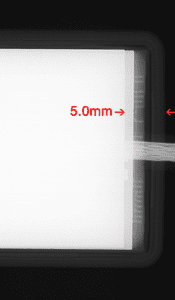

For historical reasons, most sensors place necessary electronics near the edge where the cord exits the sensor. The result is a dead space of up to 6mm, since the electronics cannot also be part of a sensor’s active imaging area. So, for bitewing purposes, the very edge used to capture the canine/premolar contact may not capture any image at all for its first 3-6mm. Clinicians who regularly place sensors instantly see this as a problem.

XDR clinicians asked for the dead space to be minimized. By moving the electronics elsewhere, XDR engineers achieved a 2mm mesial dead space, little more than the dead space common with film packets. Figure 1 shows how active imaging area at the mesial edge can help capture of the canine/premolar contact.

Figures 2a through 2d demonstrate how XDR’s imaging area extends further toward the sensor’s mesial edge. XDR has patented this approach under US #9357972B .